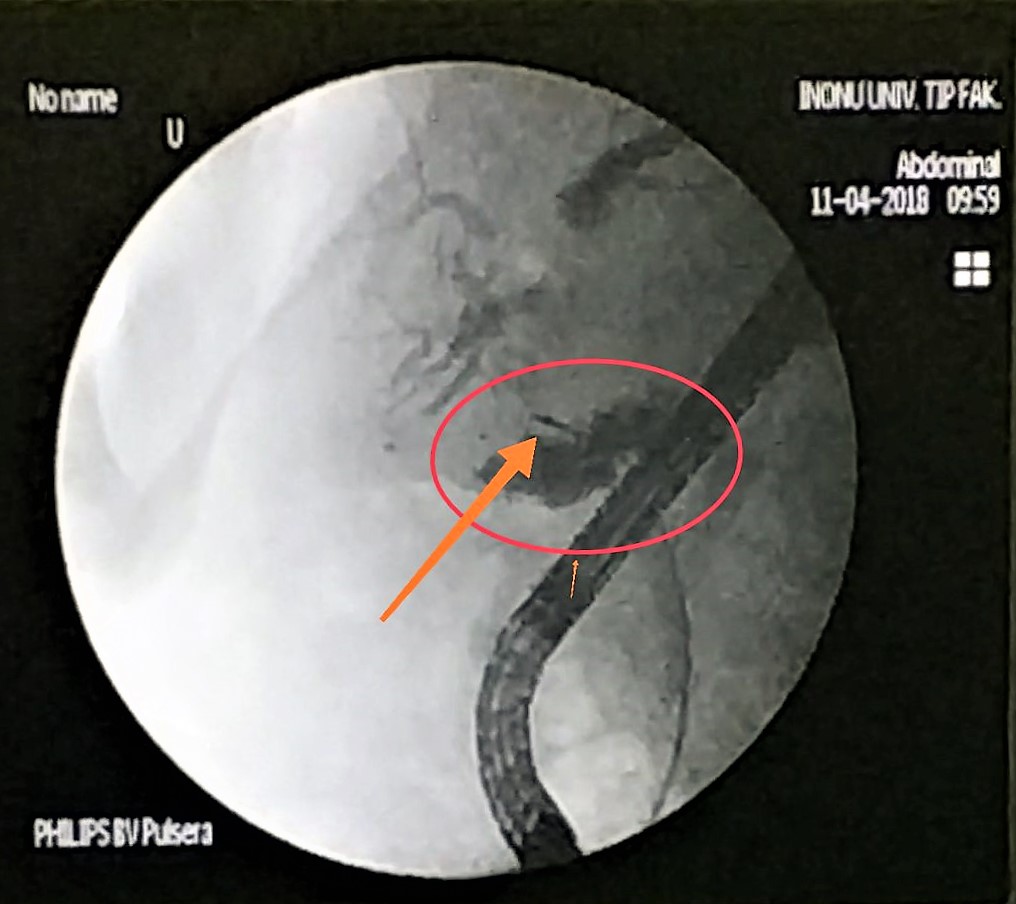

Microwave antenna in bile-duct

The doctors applied microwave energy to destroy tumor growth prior or post bile-duct stent installation to reestablish and maintain normal bile flow. The microwave energy is applied to the tumors in and around the duct and stent with percutaneous transhepatic cholangiography (PTC) using fluoroscope (real-time x-ray) images of liver, bile-ducts and gallbladder-ducts. A long flexible needle-catheter is inserted into the liver under fluoroscopy to locate and identify blockages using contrast dye. Once the blockage is identified, a smaller diameter catheter with microwave antenna is introduced into first catheter, the antenna is positioned along the duct and the microwave energy is applied using preset temperature and time durations. The antenna is retracted along the duct and the energy application is repeated until the desired length of the duct is treated. The doctors would remove the microwave catheter and verify bile-duct flow with fluoroscopy. The microwave energy application is controlled with direct temperature feedback from the ablation antenna during the procedure to ensure safety and efficacy.